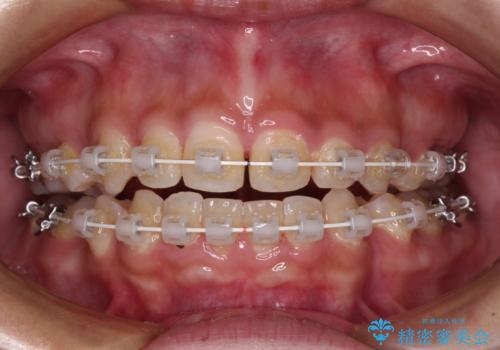

- 矯正装置

- 審美装置

- 口元の突出感と上下前歯のズレを気にして来院された患者様です。

舌の突出癖により上下の前歯は非接触であり、更には奥歯の咬み合わせが非対称となっている状態でした。

通常は上下左右の第一小臼歯4本を抜歯することになりますが、右側臼歯部の咬合が上顎前突気味であったため、下顎右側のみ第二小臼歯を抜歯し、ワイヤー装置にて矯正治療を行うこととしました。

第二小臼歯抜歯はイレギュラーな治療手段であり、治療期間が延びる傾向にありますが、舌のトレーニングをしっかりと行ってくださり、2年弱という非常に短い期間で理想的な仕上がりを達成することができました。